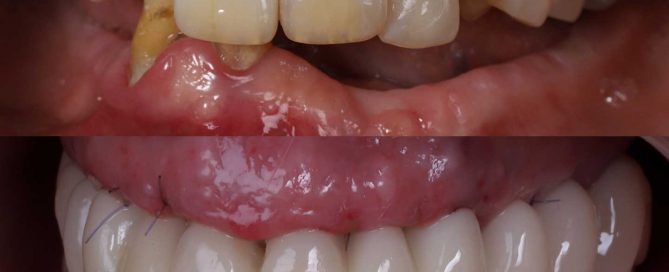

SITUACIÓN INICIAL Paciente que viene a la clínica porque no [...]